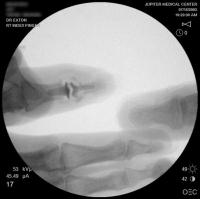

Intraoperative fluoroscopy.

Final implant radiographs.